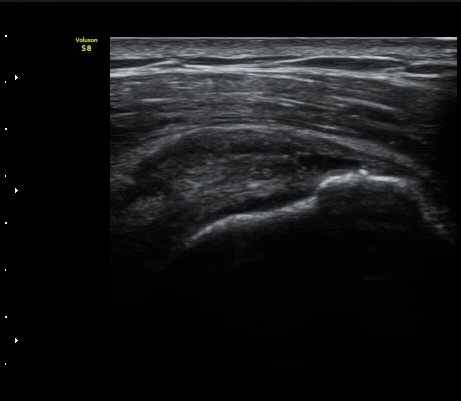

À̵ιڱ٠Ⱦ´Ü¸é°Ë»ç¿¡¼­ Á¤¸Æ³¶ÀÇ ºÎÁ¾ÀÌ °üÂûµÊ(±×¸² 1).

±Ø»ó°Ç³»Ãø Á¾´Ü¸é°Ë»ç¿¡¼­ ±Ø»ê°Ç ºÎÂøºÎÀÇ  ÀÛÀº ÆÄ¿­°ú Á¡¾×³¶ ºÎÁ¾ÀÌ °üÂûµÊ(±×¸² 2, 3).

±Ø»ó°Ç ¿ÜÃø Á¾´Ü¸é°Ë»ç ½Ã Á¡¾×³¶ ºÎÁ¾ÀÌ °üÂûµÊ(±×¸² 4).

±Ø»ó°Ç ±ÙÀ§ºÎ ±Ø»ó°Ç ³»ÃøÀÇ Àú¿¡ÄÚ ºÎÁ¾°ú Á¡¾×³¶ ºÎÁ¾ÀÌ °üÂûµÊ(±×¸² 5).